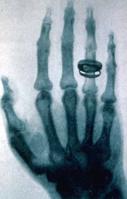

接下來更為神奇的現象發生了, 一天晚上倫琴很晚也沒回家,他的妻子來實驗室看他,於是他的妻子便成了在那不明輻射作用下在照相底片上留下痕跡的第一人。倫琴拍攝的第一張X線片當時倫琴要求他的妻子用手捂住照相底片。當顯影后,夫妻倆在底片上看見了手指骨頭和結婚戒指的影象。

倫琴拍攝的第一張X射線片接下來更為神奇的現象發生了, 一天晚上倫琴很晚也沒回家,他的妻子來實驗室看他,於是他的妻子便成了在那不明輻射作用下在照相底片上留下痕跡的第一人。倫琴拍攝的第一張X線片當時倫琴要求他的妻子用手捂住照相底片。當顯影后,夫妻倆在底片上看見了手指骨頭和結婚戒指的影象。

這一發現對於醫學的價值可是十分重要的,它就像給了人們一副可以看穿肌膚的“眼鏡”,能夠使醫生的“目光”穿透人的皮肉透視人的骨骼,清楚地觀察到活體內的各種生理和病理現象。根據這一原理,後來人們發明了X光機,X射線已經成為現代醫學中一個不可缺少的武器。當人們不慎摔傷之後,為了檢查是不是骨折了,不是總要先到醫院去“照一個片子”嗎?這就是在用X射線照相啊!